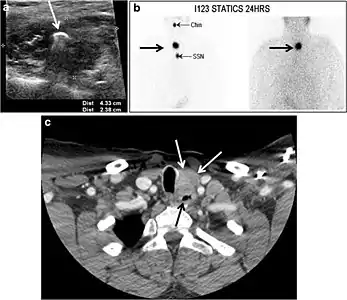

Fig. 4. A 45-year-old male patient presented with anterior mediastinal metastatic PTC lesions and occult primary on imaging. Histopathology examination of the resected thyroid gland revealed micro-foci of PTC; the largest, in the isthmus, measured 4 mm. a transverse greyscale ultrasound of the thyroid demonstrates homogeneous gland with normal echogenicity and size. No focal lesion or micro-calcifications. b Non-enhanced CT scan obtained as part of PET/CT examination shows a heterogeneous, large, relatively dense anterior mediastinal mass (white arrow) with peripheral calcification (arrowheads). Thyroid gland has normal CT appearance with no abnormal FDG uptake (not shown).[1]

Fig. 7. A 51-year-old female patient post total thyroidectomy for PTC with elevated thyroglobulin measurement. an Axial non-enhanced CT scan of the neck at the level of the thyroid bed demonstrates a well-defined, rounded, homogenously dense soft tissue situated between the trachea and left internal jugular vein (white arrow). b Transverse ultrasound image of the neck demonstrates a well-defined, homogeneous, hypoechoic soft tissue nodule measuring 6 mm (white arrow) with no detected micro-calcifications. Biopsy showed a predominantly residual normal thyroid tissue with micro-foci of PTC.[1]

Fig. 8. A 48-year-old male patient post total thyroidectomy with PTC recurrence. a Transverse greyscale ultrasound of the neck demonstrates a left thyroid bed heterogeneous, predominantly hypoechoic irregular lesion with calcifications (white arrow). b A spot image of iodine 123 total body scan of the neck demonstrate a focus of abnormal radiotracer uptake at the left thyroid bed (Black arrows) between the annotated markers. c Enhanced axial CT scan of the neck demonstrates an enhancing large left thyroid bed mass (white arrow) with no calcifications. The lesion exerts a mass effect on the oesophagus (black arrow) and is inseparable from the trachea.[1]